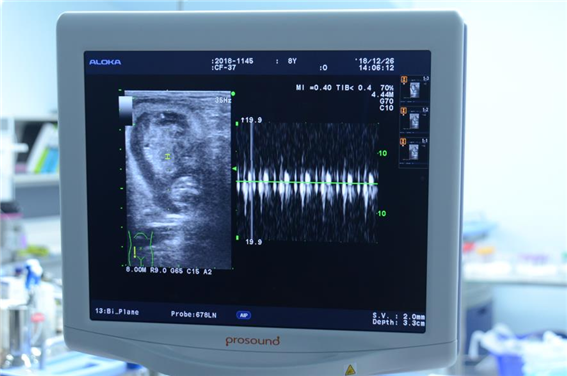

![]() |

| ▲인공수정 반달가슴곰 임신진단. |

인공수정 이후, 올해 1월 어미 2마리(KF-49, CF-37)가 각각 새끼 1마리(암컷)와 2마리(수컷 1, 암컷 1)를 출산했다.

| ▲인공수정 태아 심박동 확인. |